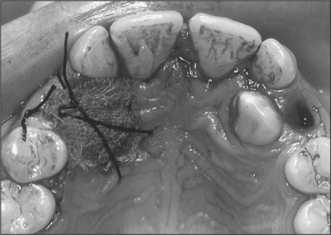

2. The patient in Fig. 12.17 presents with failed eruption of the permanent upper central incisor.

(a) At what age should this tooth have erupted? List four causes of delayed eruption.

Page 181

(b) List three local complications of surgery in this region to expose the tooth.

(c) What is the radio-opacity overlying the tooth crown?

image

Fig. 12.17 See question 2.